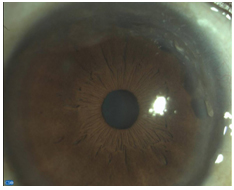

Ojo derecho: Adelgazamiento corneal periférico, que avanza desde limbo esclero-corneal, en h-10, con finos vasos superficiales, en forma de semicírculo. (Figura 4 y figura 5 )

Figura 4. Caso 2. Biomicroscopía anterior a iluminación difusa de la córnea.

Figura 5. Caso 2. Biomicroscopía anterior a iluminación focal en hendidura de la córnea.

En el caso 2 la degeneración marginal de Terrien se presenta como "opacidad marginal similar a un gerontoxon con vascularización periférica". Típicamente se presenta en el sector superior, pero puede ser anular desde el principio o evolucionar. Está formado por un fino punteado gris amarillento que afecta todo el espesor corneal en un espesor de 1-3 mm y suele estar separada del limbo por una estrecha zona transparente. La vascularización es superficial y procede de las arcadas lumbares. Cuando aparece este patrón en los pacientes de edad avanzada con adelgazamiento escaso puede tratarse de una degeneración marginal en surco idiopática o senil.3, 4